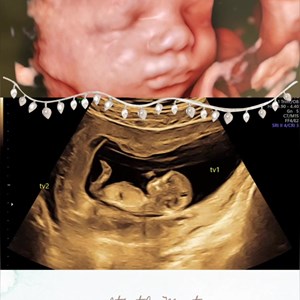

Dejlig lille suttelysten pige 3D scanning uge 33+1 med søde minder for hele familien 👀👶...

Dagens søde lille julenisse ❣️ Pige uge 30. Ca 1300 gram lækkerhed 😍

Sødeste lille pus ❣️#uge33 #3dlive #vægtscanning #babypics #hjertelyd #hjertelyd_scanning...